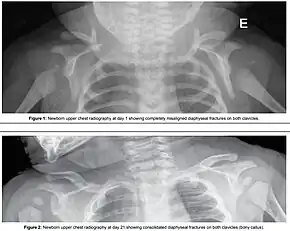

Typically the procedures are performed in the order listed and the sequence ends whenever a technique is successful.[10] Intentional fracturing of the clavicle is another possibility at non-operative vaginal delivery prior to Zavanelli's maneuver or symphysiotomy, both of which are considered extraordinary treatment measures. Pushing on the fundus is not recommended.[1]

- Intentional causing clavicular fractures, which reduces the diameter of the shoulders that requires to pass through the birth canal;[2]